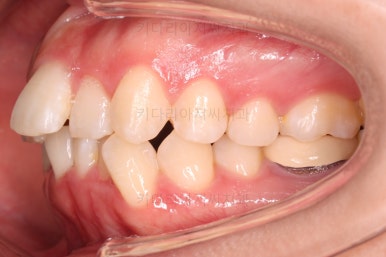

웃거나 말할 때 치열이 삐뚤어서 미적으로 별로 좋지 못하고요.

옆모습을 보면 심하진 않지만 약간 돌출입, 턱끝에 힘이 들어가서 약간 둥근 무턱의 모양입니다.